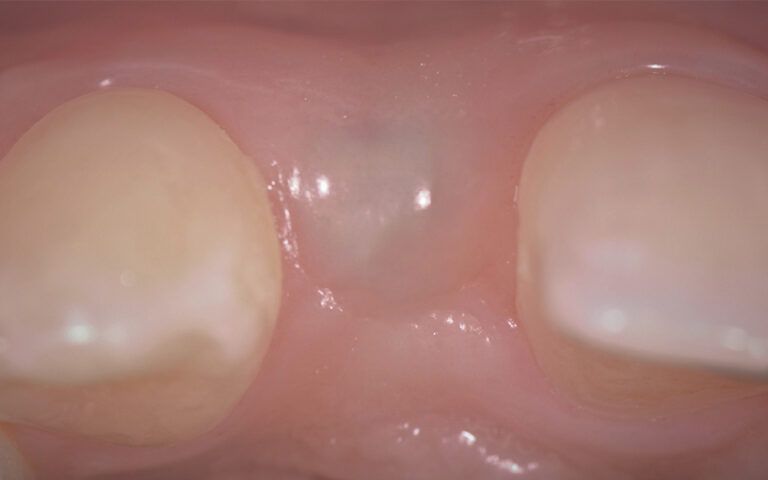

Images of the osseointegration period of the implants and healing of the tissues Images of the osseointegration period of the implants and healing of the tissues Images of the osseointegration period of the implants and healing of the tissues Images of the osseointegration period of the implants and healing of the tissues

After three months of osseointegration, the second surgery performed on both implants and the digital impressions were taken with the TRIOS (3Shape) intraoral scanner.